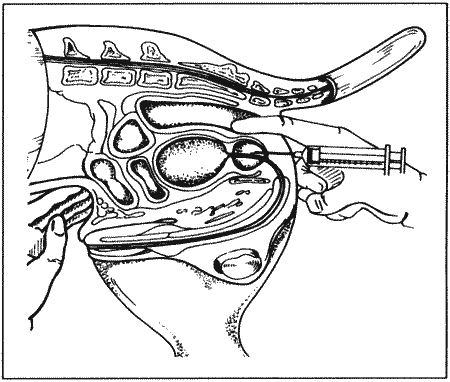

Рассматриваются следующие вопросы: нормальная физиология собак и кошек; болезни репродуктивной системы; бесплодие самок и бесплодие самцов; нормальное функционирование и дисфункция молочных желез; спаривание; искусственное осеменение; протекание беременности и роды; уход за новорожденными щенками и котятами, их наследственные и инфекционные болезни; техника оперативных вмешательств на репродуктивных органах; фармакологический контроль репродукции.

В Руководстве приводится обзор нормальной физиологии и эндокринологии размножения собак и кошек, рассматриваются причины бесплодия самок, функция и дисфункция молочных желез, нарушения, возникающие у небеременных самок, а затем столь же подробно описываются соответствующие проблемы у самцов. Далее обсуждаются вопросы спаривания и искусственного осеменения, а также протекание беременности и родов. Специальный раздел посвящен наблюдению и лечению новорожденных щенков и котят; он включает обзорные данные по наследственным порокам, обсуждение роли инфекционных болезней и мер по их предупреждению. В заключительных главах книги рассматриваются терапевтические и хирургические методы, применяемые для коррекции репродуктивных нарушений.